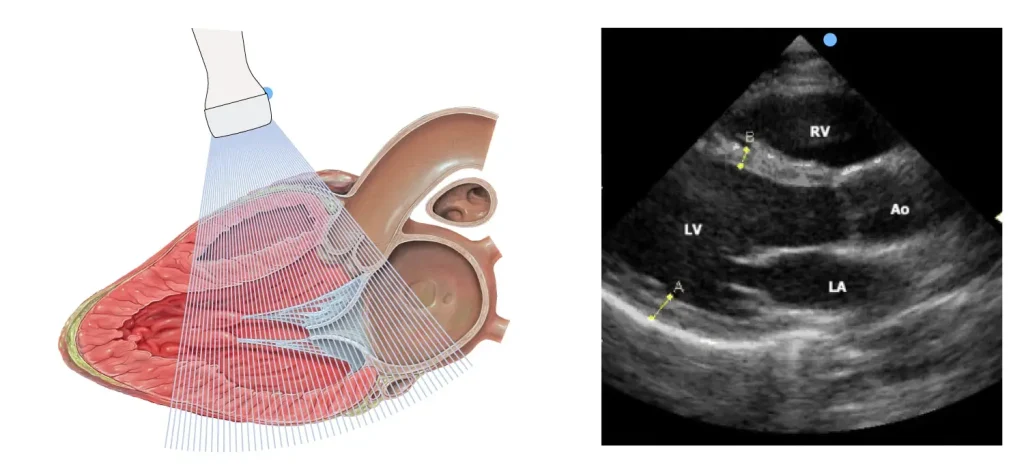

اکو قلب در واقع نوعی سونوگرافی تخصصی برای قلب است. این روش از امواج صوتی با فرکانس بالا (اولتراسوند) برای ایجاد تصاویر متحرک از قلب استفاده میکند. یک دستگاه کوچک به نام «پروب» یا «مبدل» روی قفسه سینه شما قرار گرفته و امواج صوتی را به سمت قلب ارسال میکند. این امواج پس از برخورد با ساختارهای مختلف قلب، بازتاب یافته و توسط همان دستگاه دریافت میشوند. سپس یک کامپیوتر پیشرفته این امواج بازگشتی را به یک تصویر دقیق و متحرک تبدیل میکند.

- اکو از روی قفسه سینه (Transthoracic – TTE): این رایجترین و استانداردترین نوع اکو است. پروب روی پوست قفسه سینه حرکت داده میشود و تصاویر کلی از قلب ارائه میدهد.